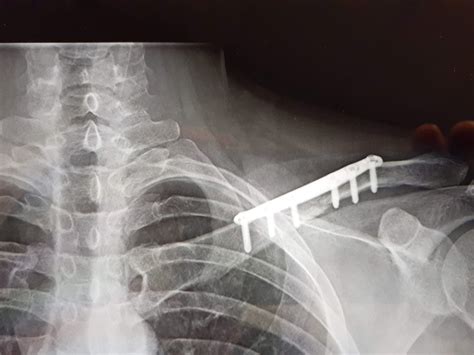

X Ray Broken Collar Bone